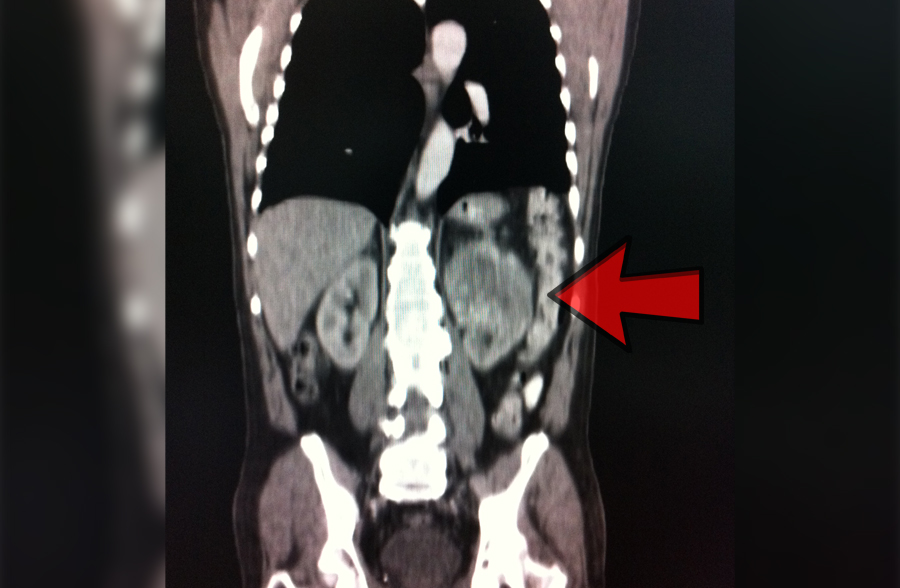

Hernia discal que causan compresión en una raíz nerviosa

Habitualmente causan mucho dolor lumbar, de tipo ciática, con debilidad para caminar y problemas de sensibilidad en los pies.

Requiere una valoración con estudio de imagen para determinar su manejo.